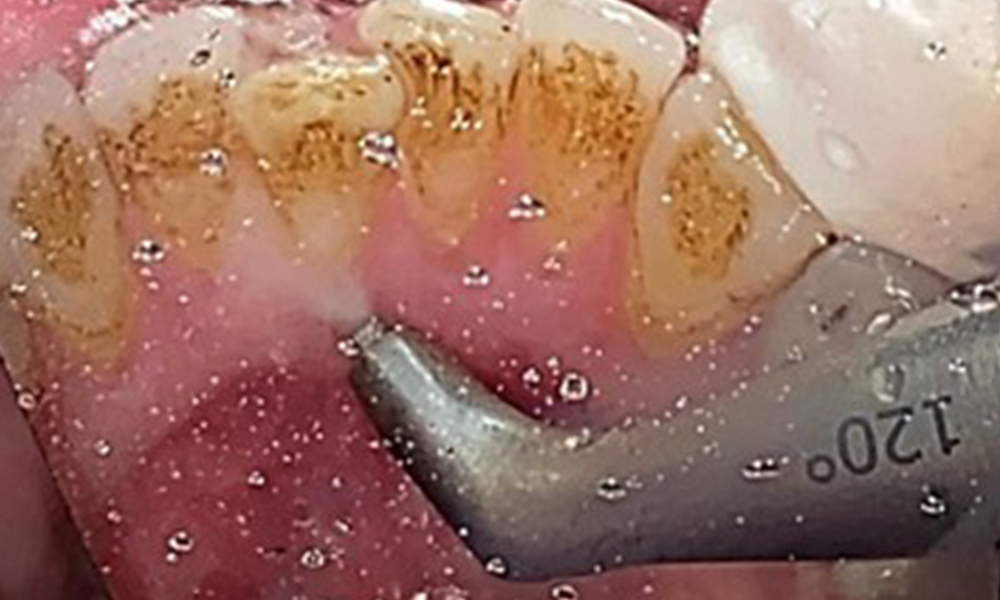

L'objectif serait de contrôler le risque de maladie en éliminant le biofilm supra-gingival et sous-gingival. Les instruments peuvent être sélectionnés en fonction des besoins du patient. Tout d'abord, le tartre et les concrétions doivent être éliminés à l'aide d'instruments ultrasoniques et/ou manuels (Fig. 10).